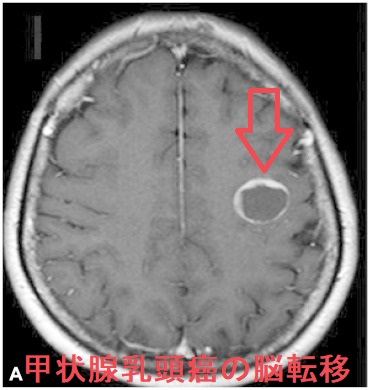

甲状腺癌分化癌(乳頭癌、濾胞癌)の脳転移は遠隔転移の約1%。脳神経症状・けいれんを起こし予後に大きく影響。単発性の場合は原発性脳腫瘍と鑑別できず、摘出後の病理標本で甲状腺乳頭癌・甲状腺癌濾胞癌の脳転移と分かる。最初から放射性ヨウ素(I-131)を取り込んでいれば放射線内・外照射、γナイフ、分子標的薬で治療。下垂体腫瘍で中枢性甲状腺機能低下症(非機能性下垂体腫瘍のほとんどが血清TSH基準値内)。ACTH産生腫瘍は中枢性甲状腺機能低下症を起こし易く、成長ホルモン(GH)産生腫瘍(先端巨大症)は起こし難い(いずれも約50%で血清TSH基準値内)。

甲状腺癌の脳転移は約1%と稀。半数が甲状腺未分化癌、もう半数が甲状腺癌分化癌(乳頭癌、濾胞癌)[J Neurooncol. 2001 Jan;51(1):33-40.]。

甲状腺癌脳転移の診断は、

- 脳CT/MRI

単発性の場合、原発性脳腫瘍と鑑別できず、脳外科で開頭し顕微鏡下で腫瘍摘出。病理標本で、甲状腺乳頭癌による転移性脳腫瘍と分かります。開頭手術後のQOLは、かなり改善するとされます[N Engl J Med. 1990 Feb 22;322(8):494-500.]。